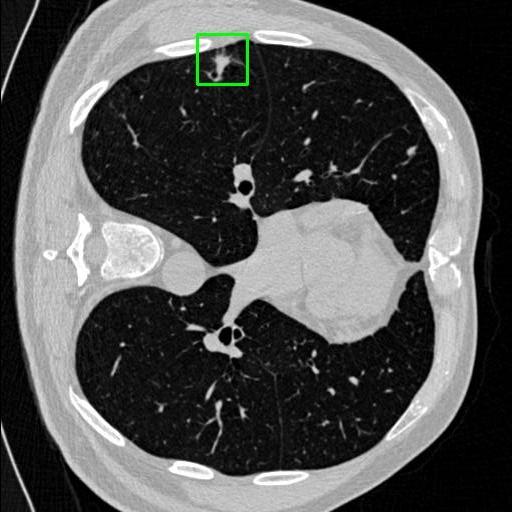

We developed an AI-based system using deep learning models for analyzing lung CT scans to detect and classify pulmonary nodules. We chose the YOLOv11 architecture for its enhanced object detection capability and adapted it specifically for medical imaging, incorporating pixel-level precision and severity classification.

Classification into three severity levels with colored bounding boxes.

Successfully built and deployed an AI model (YOLOv11) capable of detecting lung nodules in CT scans with high accuracy and real-time performance.

Designed a severity classification system that categorizes nodules into null, moderate, and severe using colored bounding boxes, assisting in rapid clinical decision-making.